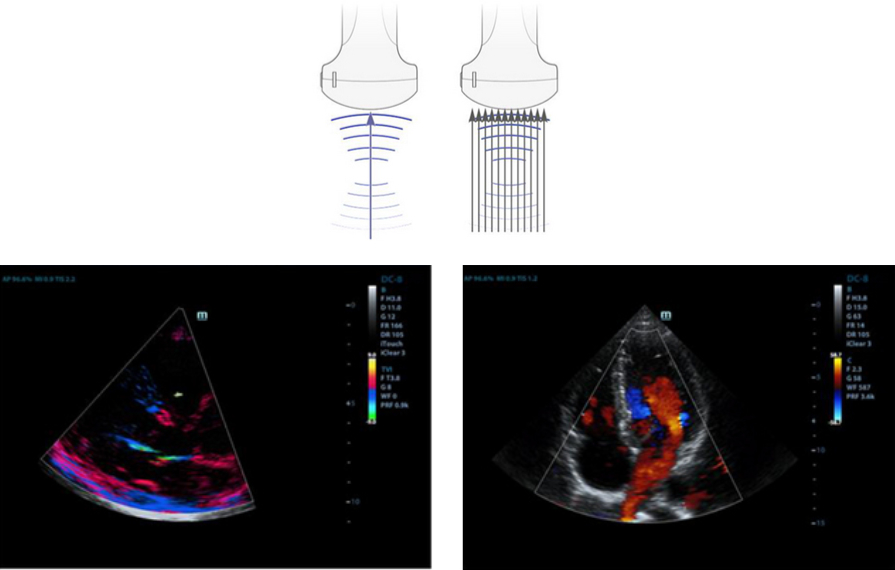

?oklu I??n Olu?turma

Sonucunda mĂŒkemmel zamanlama ??zĂŒnĂŒrlĂŒ?ĂŒ ve daha yĂŒksek resim karesi h?z? elde edilen, tek bir aktar?lm?? ???n i?in maksimum 12 defa i?lem sĂŒresi.

iBeam?

Sonucunda art?r?lm?? kontrast ??zĂŒnĂŒrlĂŒ?ĂŒ ve geli?mi? g?rĂŒntĂŒleme imkan?na kavu?ulan tek bir g?rĂŒntĂŒ olu?turmak i?in bir?ok tarama a??s?n?n kullan?lmas?na izin verir.